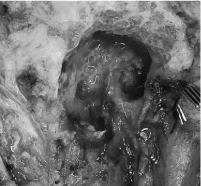

Following a discussion with the multidisciplinary tumor board, a right radical parotidectomy, ipsilateral selective neck dissection (levels II/III and VA) with possible temporal bone resection, facial nerve sacrifice and nerve grafting was recommended. During the procedure, frozen section pathology confirmed invasion of the facial nerve at the level of the stylomastoid foramen (Figure 3). As such, the facial nerve was sacrificed and removed en bloc with the tumor. Temporal bone resection was performed with frozen sectioning of the proximal facial nerve to confirm a negative margin and to have a proximal stump for nerve grafting (Figure 4). Nerve grafting was completed as planned with ansa cervicalis to marginal mandibular branch, masseteric nerve to zygomatic branch and facial nerve mastoid stump to the upper branches of the facial nerve using a cable graft from the nerve to vastus lateralis (Figure 5). The defect was reconstructed with a left anterolateral thigh free flap for volume restoration/coverage and a gold weight was inserted into the upper eyelid to enable eyelid closure.

Figure 3. Post-auricular flap exposure and dissection of facial nerve root (white triangle) adherent to parotid tumor at the level of the stylomastoid foramen. Thickened appearance of facial nerve indicative of invasion